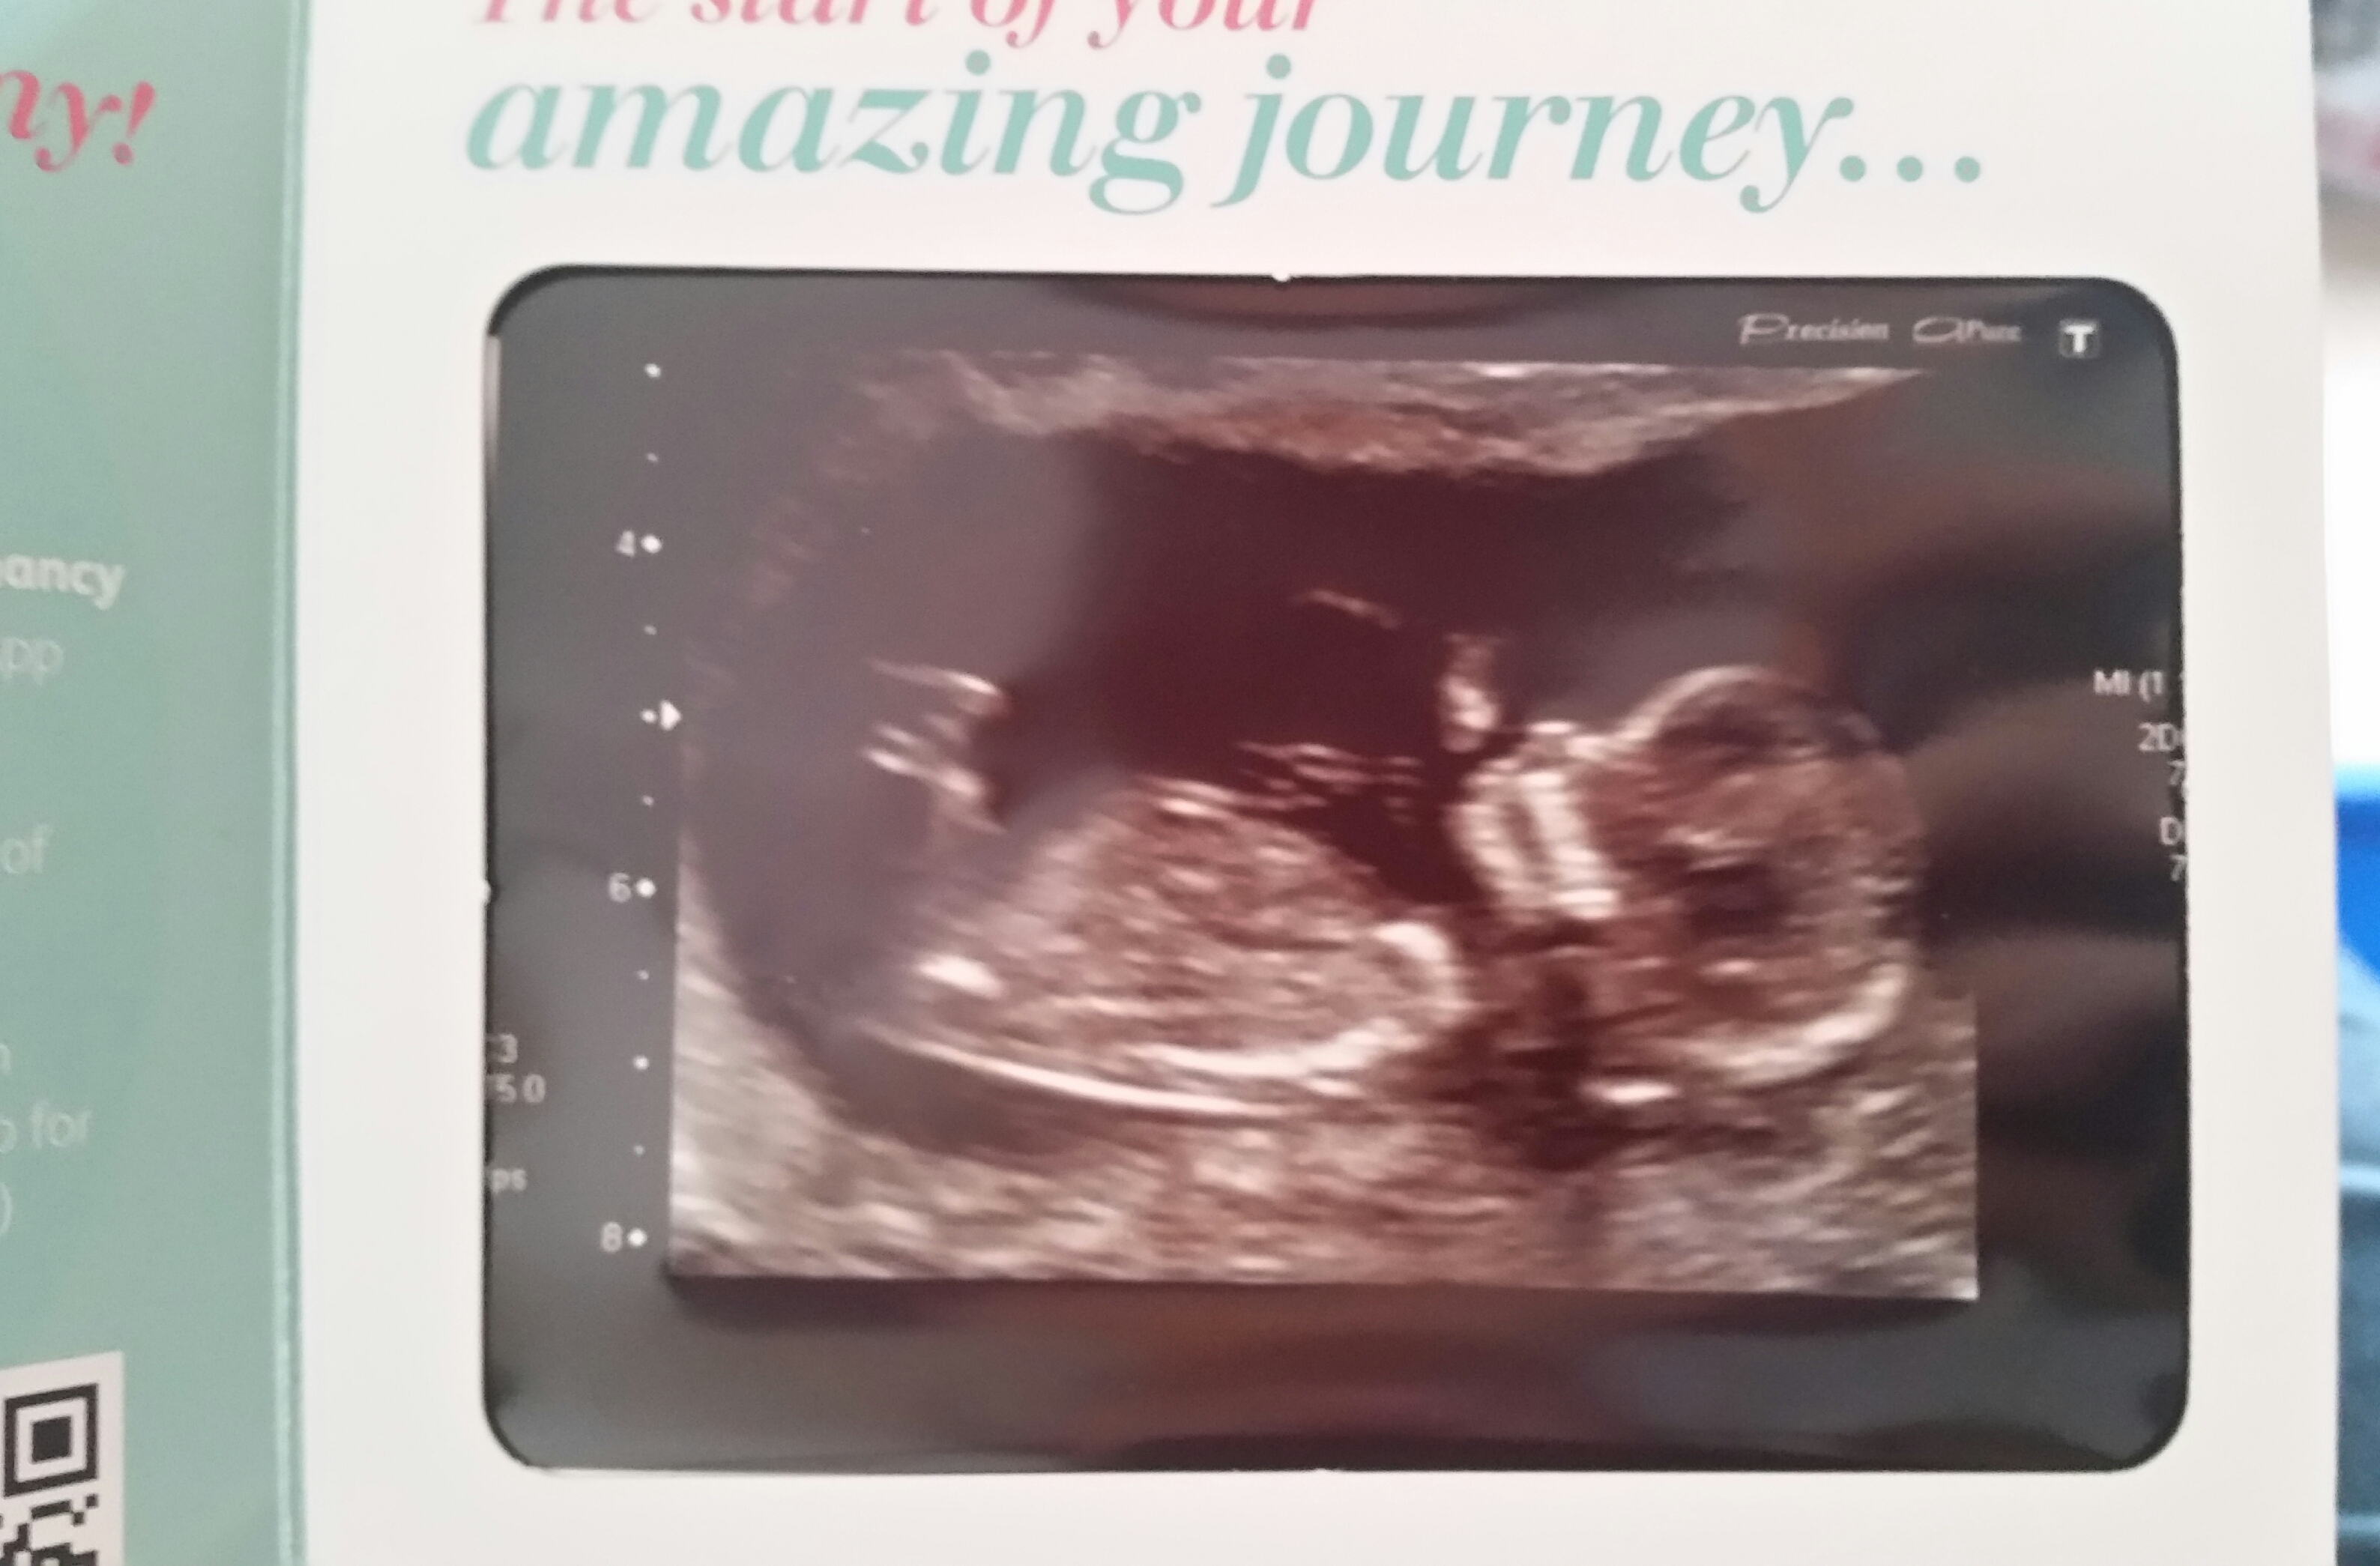

Hey everyone.. I posted a while back asking for some gender predictions..I was told a number of times there was no nub on my scan picture... However. .. A member of another forum played around with the image and thinks she can indeed see a nub. She said if it was she would lean towards a girl... she said the spine isn't straight and to bare that in mind and follow the line of the spine which makes the nub almost parallel... would love to know your thoughts

Can anyone give me an idea? Would love to hear what you think.... nub or not xxxx

Yes, that's a nub, maybe girl?

That's what others have said as it's going in the same direction as the spine, thank you for replying ☺☺☺